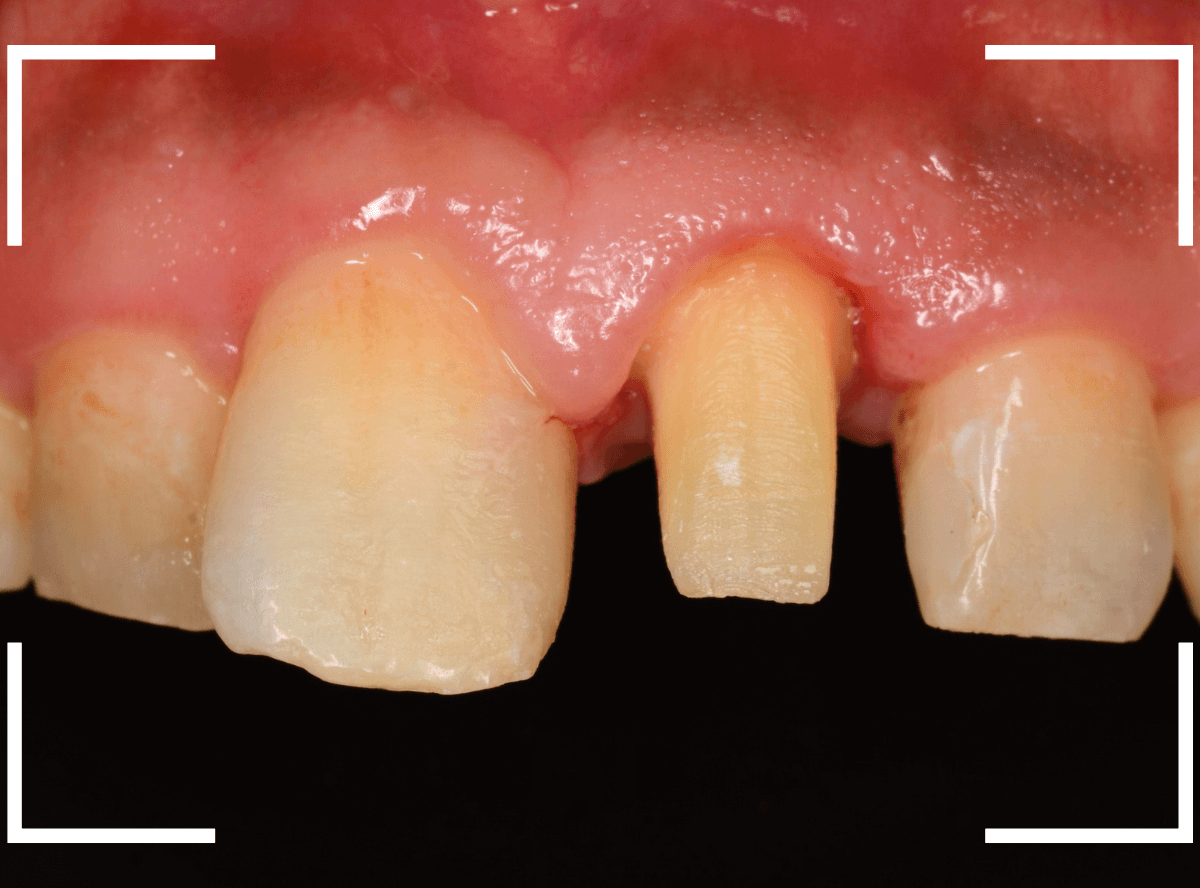

Case.16 保険のさし歯(レジン前装冠)をジルコニア・セラミックへ

以前に治療した上のさし歯を綺麗にやり直したいというご相談の患者さんです。

保険診療で行うさし歯「レジン前装冠」が入っています。

「レジン前装冠」は裏から撮影した写真を見ていただければわかるように、銀歯の上にレジン(プラスチック)を盛ったさし歯で、実質的には銀歯です。

銀歯の上にプラスチックを盛るために、歯をかなり大きく削る必要があったり、短期間で劣化・変色する(この方の差し歯も劣化してのっぺりした黄土色になっています)、金属の色素が歯肉に溶け出して歯肉が黒くなる(メタル・タトゥー)などのデメリットがあります。

さて、この方の歯の形を確認すると、左右でかなり歯の長さに差があります。